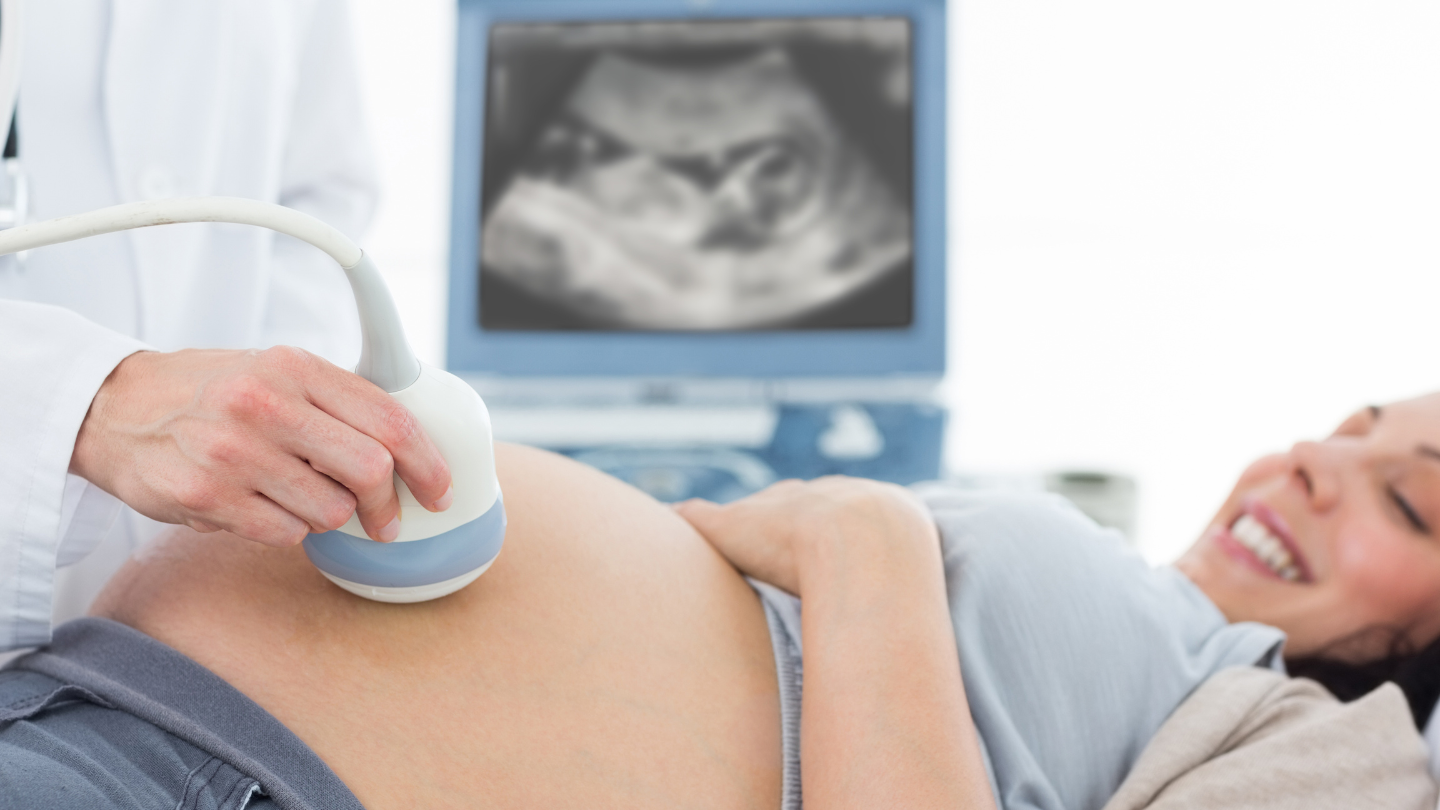

Chỉ số thai 37 tuần mẹ bầu cần theo dõi

Các chỉ số thai 37 tuần là căn cứ quan trọng để đánh giá sự phát triển của bé:

- Cân nặng thai nhi: Khoảng 2,8 - 3,4 kg.

- Đường kính lưỡng đỉnh (BPD): Khoảng 90 - 93 mm.

- Chu vi vòng đầu (HC): Khoảng 320 - 340 mm.

- Chu vi vòng bụng (AC): Khoảng 310 - 340 mm.

- Chiều dài xương đùi (FL): Khoảng 70 - 75 mm.

- Nhịp tim thai: 110 - 160 lần/phút (bình thường, có thể biến đổi nhẹ).

Ngoài ra, bác sĩ sẽ theo dõi các đặc điểm sau:

- Lượng nước ối (chỉ số AFI bình thường).

- Tình trạng bánh nhau và dây rốn.

- Dòng chảy động mạch rốn.

Nếu các chỉ số nằm trong ngưỡng bình thường, thai nhi được đánh giá là phát triển tốt ở thai 37 tuần. Mẹ nên tái khám định kỳ để theo dõi sát sao.